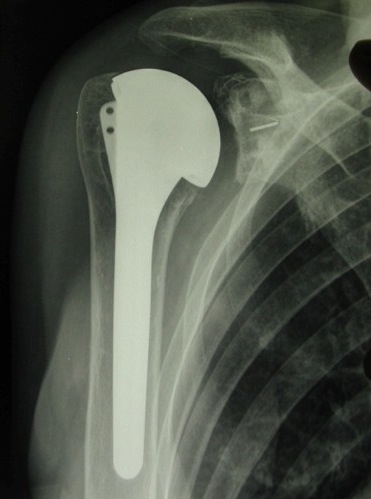

Une prothèse anatomique implique deux temps :

le remplacement de la tête humérale

par une portion de sphère pleine (ou creuse dans certains cas comportant un resurfaçage de la tête) fixée sur une tige introduite dans la cavité medullaire de l’humérus.

Ce temps est identique à une prothèse partielle humérale ou de resurfaçage

La tige est commune à toutes les configurations de prothèse (humérale simple, anatomique, inversée). Elle est dite « modulaire ».